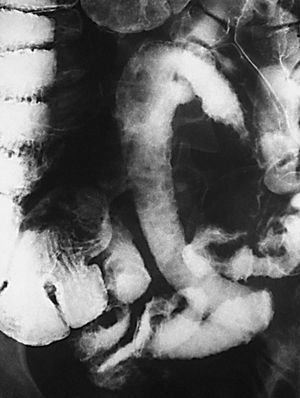

La EC se define como un proceso transmural inflamatorio crónico de etiología desconocida. De carácter recurrente, segmentario y granulomatoso, tiende a provocar complicaciones tales como abscesos y trayectos fistulosos. Se localiza en cualquier segmento del tracto digestivo, desde la boca al ano, aunque asienta de forma preferente en el íleon terminal, en íleon proximal y colon ascendente (fig. 1). Se acepta que en un 55% de los casos hay afectación del íleon terminal y del colon, en un 30% de los casos sólo de intestino delgado y que la afectación exclusiva del colon acaece en un 15%9.

Fig. 1.--Enfermedad de Crohn, afectación segmentaria del tracto digestivo con localización duodenal (A) e ileal (B) en el mismo paciente.